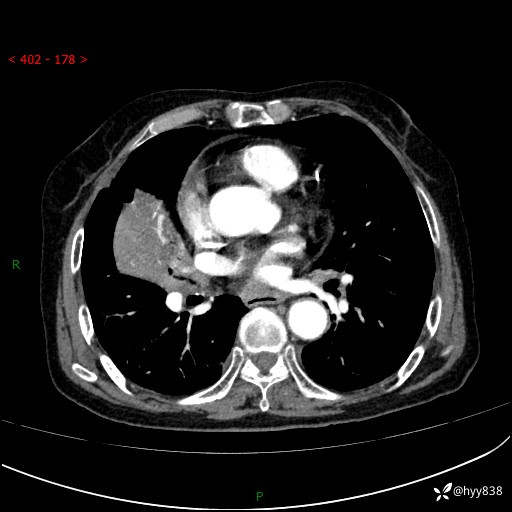

胸部CT增强(外院平扫)